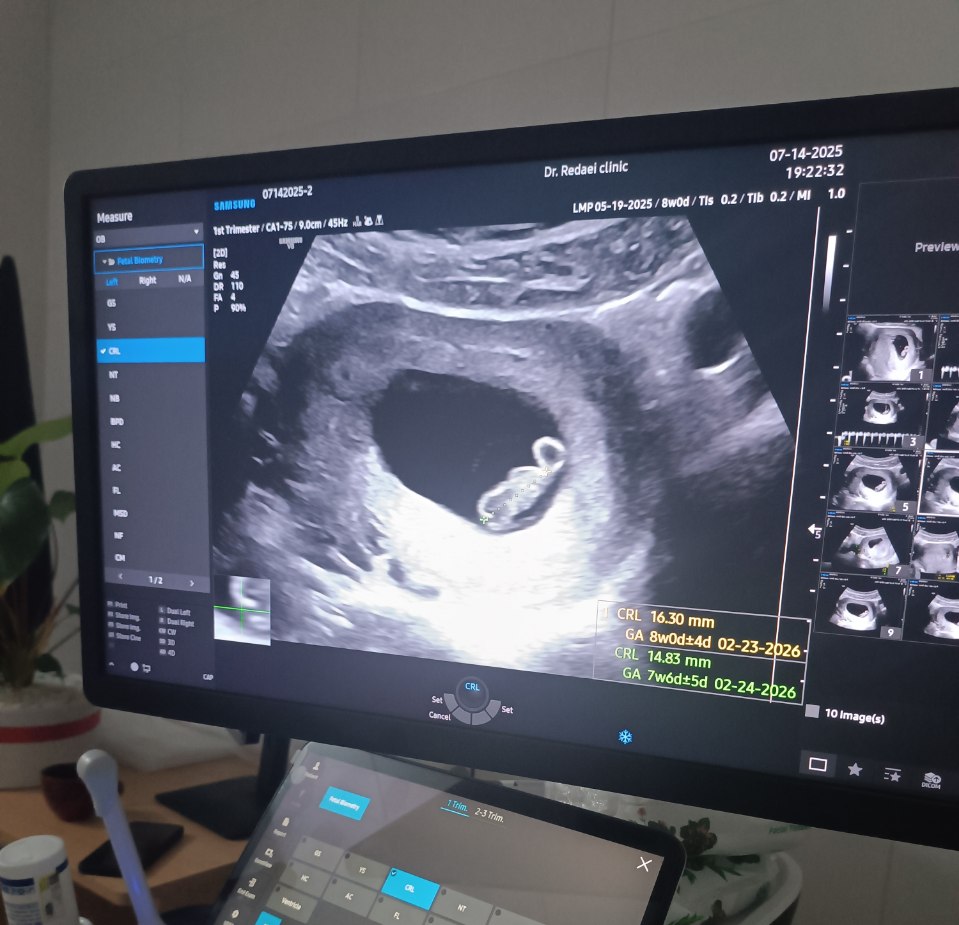

اوایل این ماه وسط تمام اتفاقاتی که داشت تو سطح کشور و دنیا میافتاد متوجه اتفاقی عجیب در زندگی خودم شدم. متوجه شدم من دیگه اون آدم سابق نیستم و چیزی به وجودم اضافه شده که از اینجا به بعد تمام ابعاد زندگیم رو تحت تاثیر قرار میده. آره درسته، متوجه شدم دارم مادر میشم. هضم این اتفاق اینقدر برام سنگین بود که تا روزها تو شوک بودم و نمیدونستم باید چیکار کنم. از اون روز تمام دغدغهام این شد که بفهمم از الان چه مسئولیتهایی دارم و چه تغییراتی باید تو تغذیه، فعالیتهای روزمره، رفتارم، حتی روتین پوستیم و ... بدم. اولین قدم این بود که یه سری اپلیکیشن بارداری نصب کنم تا بفهمم کلا چه خبره و چه اتفاقی داره میفته. قدم بعدی چکابها و آزمایش و سونوهایی بود که از سلامتش مطمئن بشم و بعد هم خبر دادن به آدمهای خیلی نزدیکم. ولی در تمام این لحظهها حسی داشتم که قابل توصیف نیست؛ ترکیبی از هیجان و خوشحالی و احساس مسئولیت با چاشنی نگرانی... که باعث میشد آروم نگیرم و مدام در حال سرچ کردن و خوندن در مورد چیزهایی که نمیدونم بشم.

دیگه گفتن نداره که دلخوشی عمده ام تو این ماه چی بوده. یخوام چندتا از قشنگترین صحنههای این ماه رو بگم؛ یکیش شنیدن صدای قلب بچه از سونوگرافی و دیگری خبر دادن به خانوادهها و دیدن ذوق و خوشحالیشون بود. مثلا وقتی به پدرم خبر دادیم خیلی خسته بود اما تا فهمید بدو بدو از خونه زد بیرون و با شام و شیرینی برگشت. نمیدونم جای اونا بودن چه حالی داره. خیلی دوست داشتم که این روزا مادرم هم بود و این حال و هوا رو تجربه میکرد. اما دیگه چه کنیم که گدشته رو نمیشه تغییر داد و باید از داشتههامون لذت ببریم. مثل مادر همسرم که این روزا از مادر برام مهربونتر بود و اینقدر هوامو داشت که نمیدونم محبتش رو چطور میتونم جبران کنم.